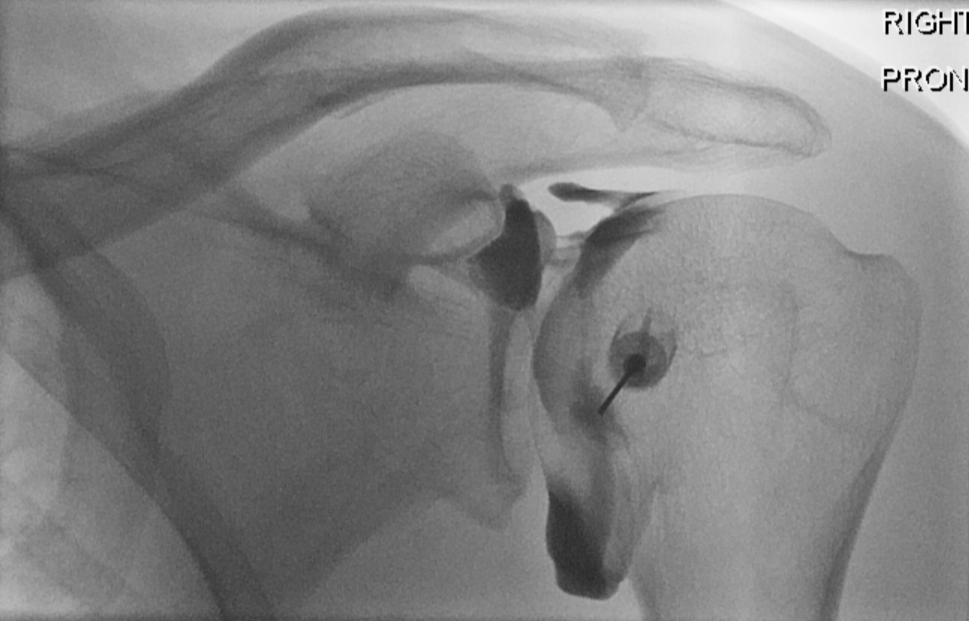

3. Shoulder glenohumeral arthrogram